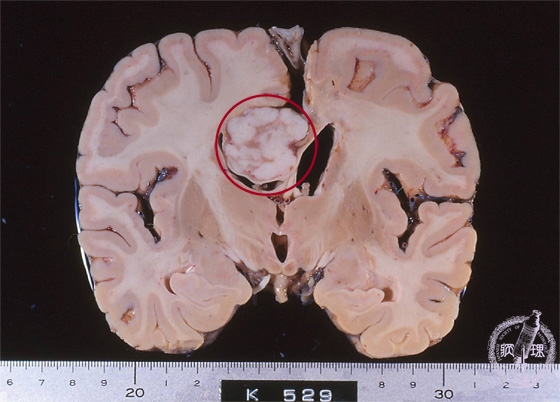

- ★(9)Meningioma

Macroscopic findings: Meningioma arising in the cerebral falx (red circle). The well-circumscribed whitish tumor compressed right lateral ventricle downword